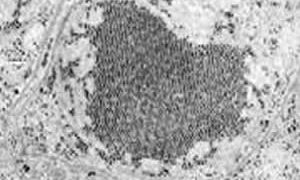

馬ヘルペスウイルス(EHV)は、二本鎖のDNAウイルスで、世界中で少なくとも9種類のウイルスが確認されています。EHVは、世界中の馬産業のあらゆる分野において、経済的にも福祉的にも大きな影響を与えています。他の種のヘルペスウイルスと同様に、...